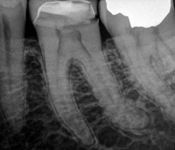

Pictured: Preoperative and Postoperative

Our patient presented with severe pain and required emergency root canal treatment. After cleaning and removing the inflamed pulp, the root canal system was successfully restored and the natural tooth saved.